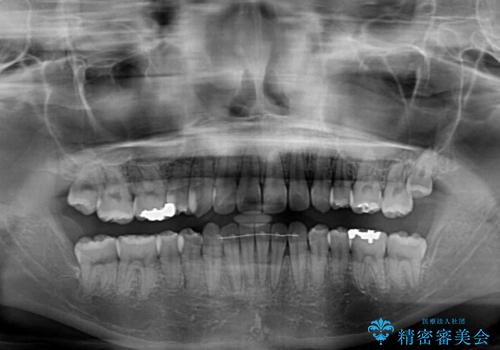

- 下の前歯のデコボコを気にして来院された患者様です。

来院当初、上顎の八重歯は気にしていらっしゃらなかったのですが、矯正治療をするのであれば、しっかりと治した方が良いと説明し、全顎矯正を行うこととしました。

八重歯の移動量が多く、インビザライン単体での治療は困難と判断し、補助装置により八重歯移動後にインビザラインを用いることとしました。

装着時間をしっかりと守ってくださったので、予定通りの期間で終了することができました。